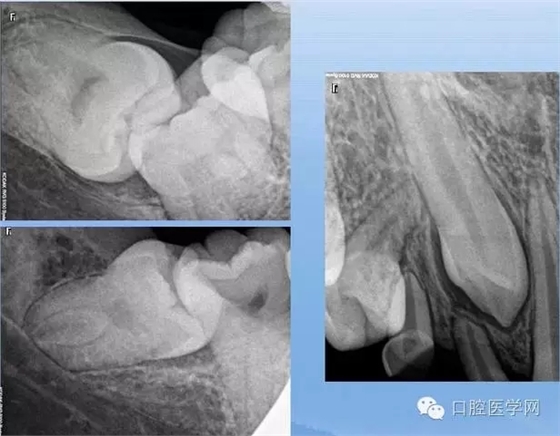

融合牙

X線表現(xiàn):牙根、牙冠完全融合額;牙根融合;牙冠融合

牙根異常(數(shù)目異常、形態(tài)異常)

X線表現(xiàn):恒磨牙及上頜雙尖牙多見,注意頰舌側(cè)根重疊雙層牙周膜影響,確定牙根變異的類型和程度。